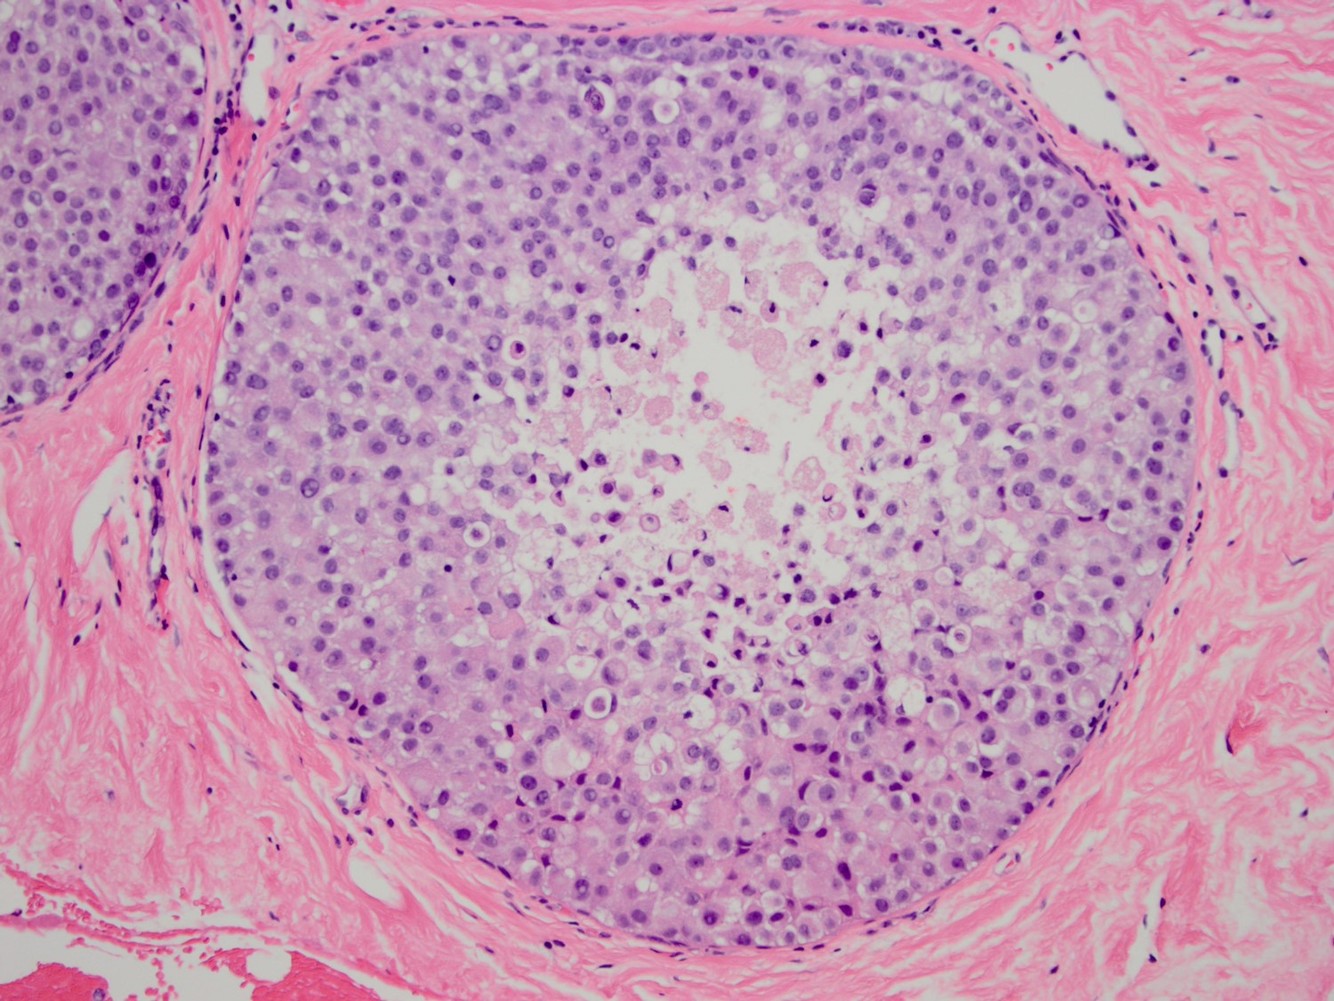

most common benign breast tumor that is well-circumscribed, slow-growing and mobile, and affects women age 20-40

fibroadenoma

*note the stromal and epithelial proliferation (below)